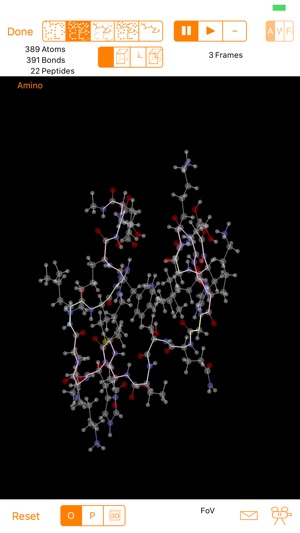

Folding@home is a project run by Stanford University managing a distributed computing setup based on computing power provided by individuals like you and me.

It use mathematical methods of protein folding to help find cures for diseases like Alzheimer's, ALS, Huntington's, Parkinson's disease and some kind of cancers.